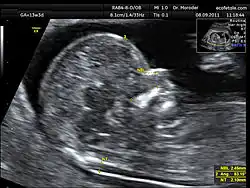

Die Messung der Nackentransparenz kann zwischen 11+0 und 13+6 Schwangerschaftswochen per Ultraschall vorgenommen werden (bzw. bis zu einer Scheitel-Steiß-Länge des Kindes von max. 84 mm); die besten Ergebnisse werden erzielt, wenn die Untersuchung mit 12 Schwangerschaftswochen durchgeführt wird. Ob der Ultraschall vaginal (über die Scheide) oder transabdominal (über die Bauchdecke) gemacht wird, ist dabei egal, denn die Ergebnisse unterscheiden sich nicht wesentlich. Der Untersuchungsablauf unterscheidet sich für die Schwangere nicht von sonstigen Ultraschalluntersuchungen und ist nach heutigem Wissensstand weder für die Schwangere noch für das ungeborene Kind schädlich.

Zur Berechnung der Ausprägung der Nackentransparenz wird das Ungeborene im Sagittalschnitt, d. h. in der Seitenansicht mit Messansatz parallel zur Mittelachse, per Ultraschall dargestellt. Das Baby sollte möglichst den gesamten Ultraschallmonitor ausfüllen, seine Wirbelsäule sollte unten liegen und sein Kopf darf sich weder in der Flexionsposition noch in der Hyperextensionsstellung befinden.